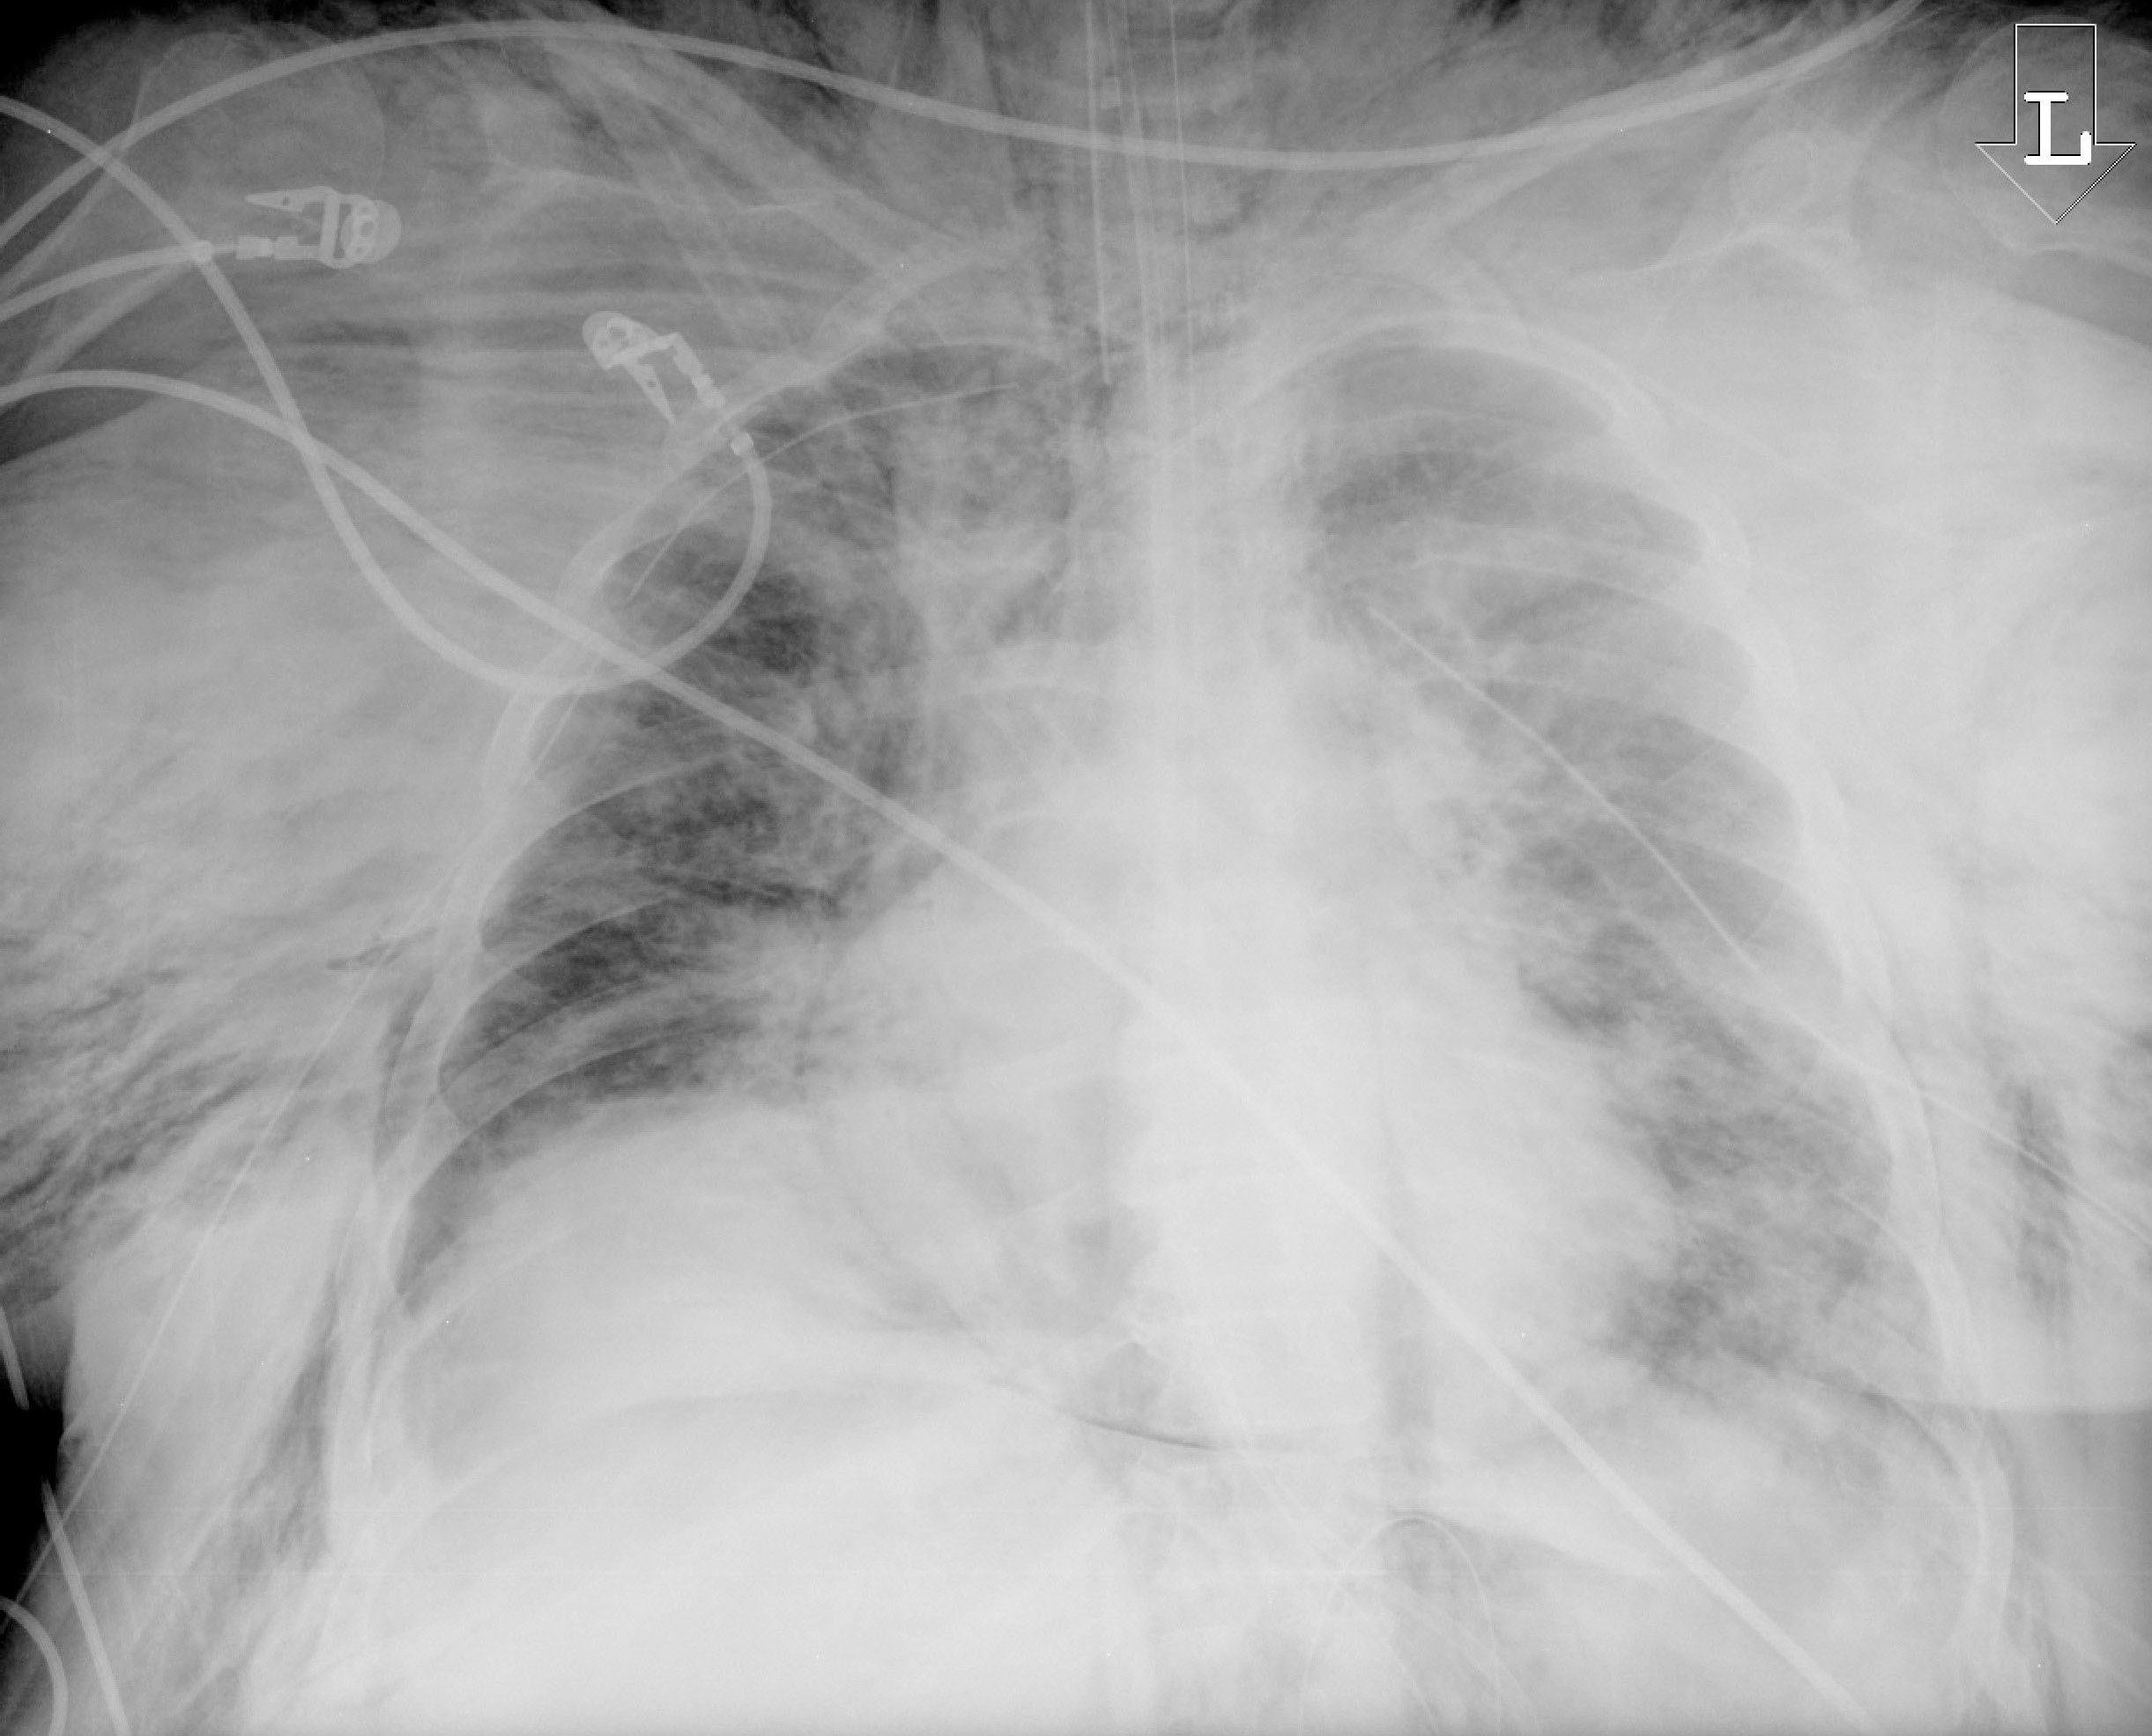

Figure 3. Subcutaneous Emphysema Due to Malpositioned Tracheostomy Tube |

Chest X-ray displaying a massive subcutaneous emphysema from a malpositioned tracheostomy tube that developed while the patient was on the ventilator. The tracheostomy tube was replaced by an endotracheal tube. |